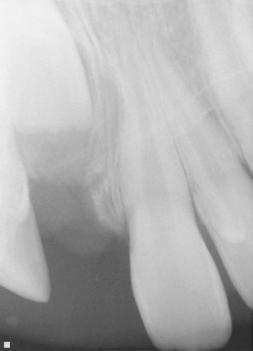

The following procedures were accomplished under general anesthesia on an outpatient basis — full mouth dental radiographs and a comprehensive oral exam. A complex odontoma was found to be the etiology of the noneruption of the maxillary right permanent central incisor (Figure 2). Since dental caries also was diagnosed, a full-mouth prophylaxis was completed. Dental caries was controlled, and teeth were restored. A 5 mm incision was made on the gingiva over the impacted maxillary right permanent central incisor, and two tooth-like structures were extracted from the right maxillary incisor area. A postoperative periapical radiograph was taken to confirm complete odontoma removal (Figure 3). Three interrupted sutures using 3-O chromic gut were placed.

Figures 2 and 3: 2. Periapical radiograph of involved area taken in the operatory during initial dental rehabilitation under general anesthesia (left). 3. Periapical radiograph of involved area taken in the operatory during initial dental rehabilitation under general anesthesia immediately after odontoma removal (right)